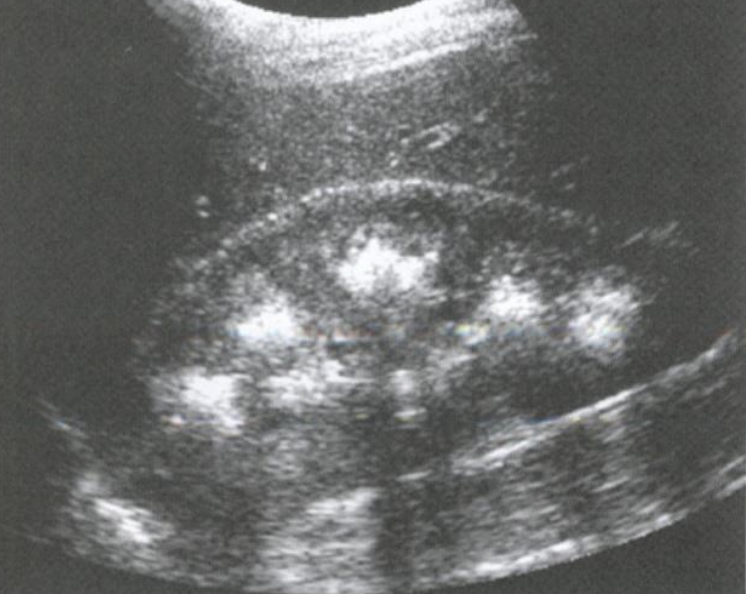

Nephrocalcinosis → calcium deposits in kidney parenchyma

2D US: pyramids more echogenic than cortex, echogenic halo around pyramids

color doppler: avascular

DDX: